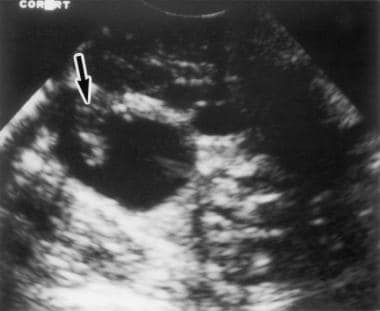

난소암은 자궁의 양쪽에 위치해 있어 난포 생산 및 여성 호르몬을 만드는 난소에 형성된 암을 뜻합니다. 대부분 발생하는 주 연령은 50대이며, 부인과 암의 약 20%를 차지하는 여성 암 사망률 1위인 무서운 질병입니다.

난소암은 초기증상이 거의 없기 때문에 환자의 절반 이상이 전이가 일어난 상태에서 의료기관에 방문하여 암을 진단받게 되며, 암이 어느 정도 전이했는지에 따라 난소암의 생존율이 달라지게 됩니다.